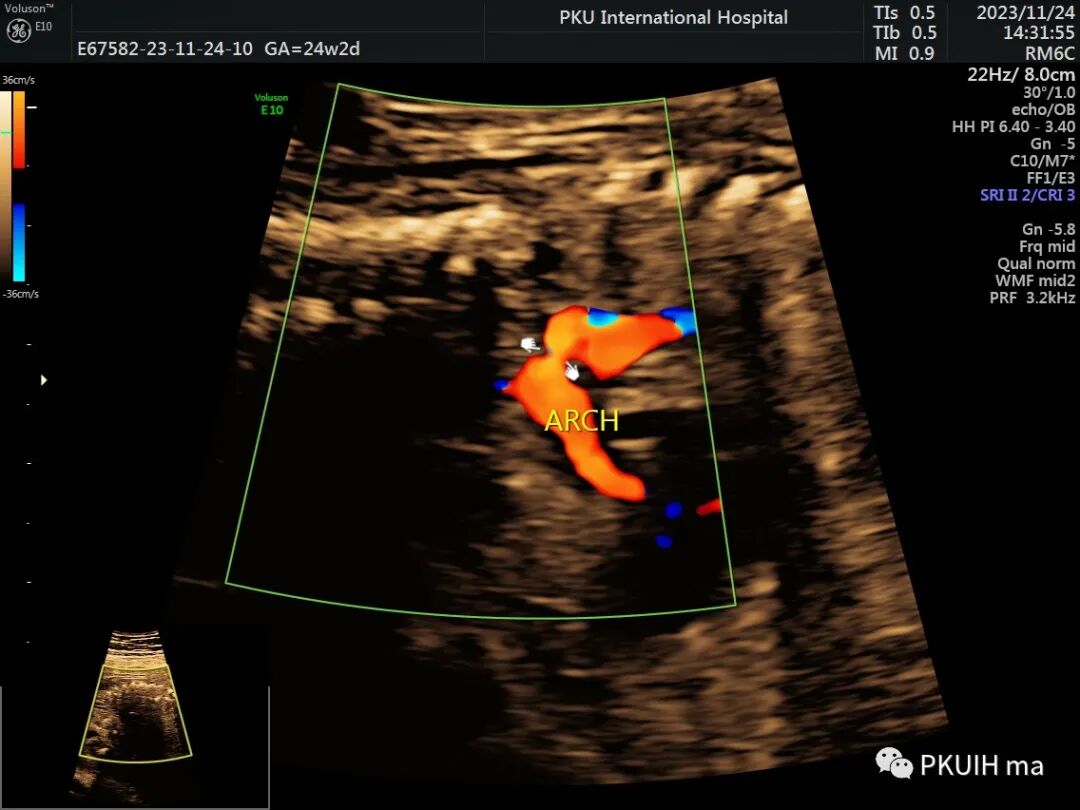

下面几张图是正常的主动脉弓长轴二维及血流图像